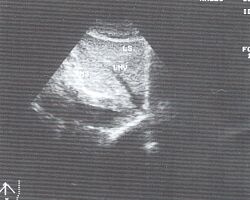

6.Сегментарное строение печени при ультразвуковом исследовании. Сегментарное строение печени - важная часть ультразвукового исследования, поскольку информация о том, в каком сегменте органа располагается поражение имеет большое значение. Печень может быть разделена печеночными венами следующим образом: правая вена делит правую долю на два сегмента - задний и передний (рис. 10) и левая вена разделяет левую долю на латеральный и медиальный сегменты (рис. 11). Теперь, если мы проведем продольные плоскости через левую, среднюю и правую главные воротные вены (рис. 12), то печень будет разделена на восемь сегментов (рис. 13).